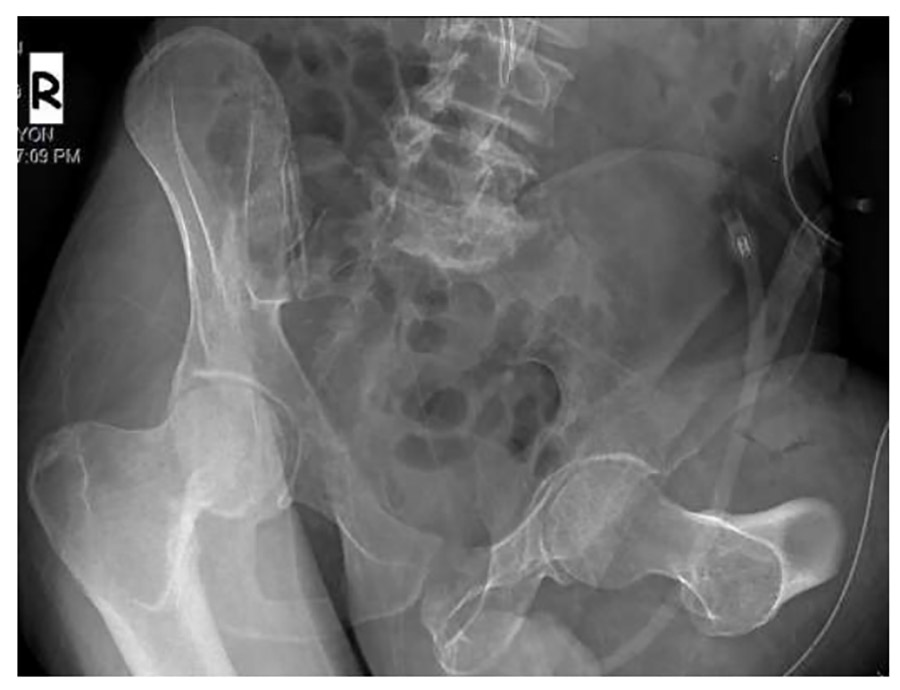

Ameliyat Sonrası: Röntgende yüksek uyluk amputasyon uygulandığı görülmekte